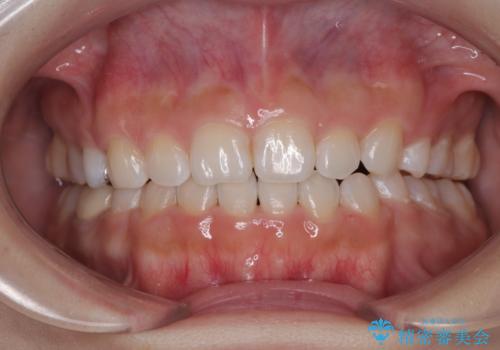

矯正治療後には、目立っていた奥歯の銀歯をオールセラミッククラウンへ作り替え、スッキリした口元に仕上がりました。